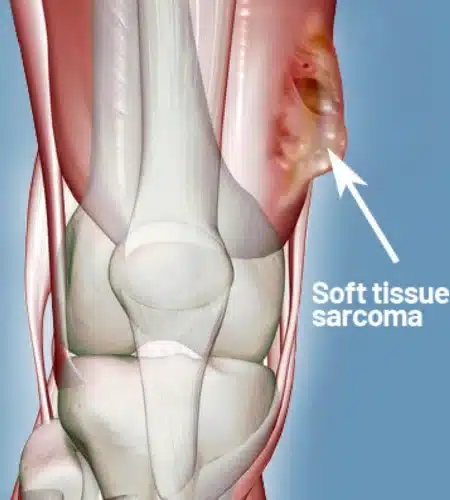

A closed needle biopsy is much safer and less invasive than an open biopsy. It minimizes the risk of the tumor spreading to surrounding tissues, creates a smaller scar, and allows for faster recovery. Crucially, a poorly planned open biopsy can sometimes make limb-saving surgery impossible later on. For more details visit Dr. Pradeep.

No, you should never remove a lump without knowing exactly what it is. If the lump is a sarcoma (cancer), “shelling it out” without a proper margin can leave cancer cells behind and lead to recurrence. Always consult an orthopedic oncologist for a proper evaluation and biopsy first. For more details visit Dr. Pradeep.

Not anymore. With advancements in technology and “Limb Salvage Surgery,” roughly 90-95% of patients can save their limbs. We remove the tumor and reconstruct the bone using metal implants or bone grafts, preserving both the appearance and function of the limb. For more details visit Dr. Pradeep.